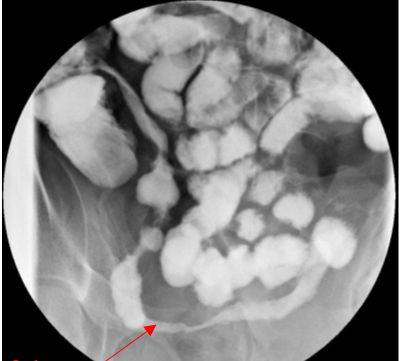

this image shows UC or CD? why?

CD: strictures